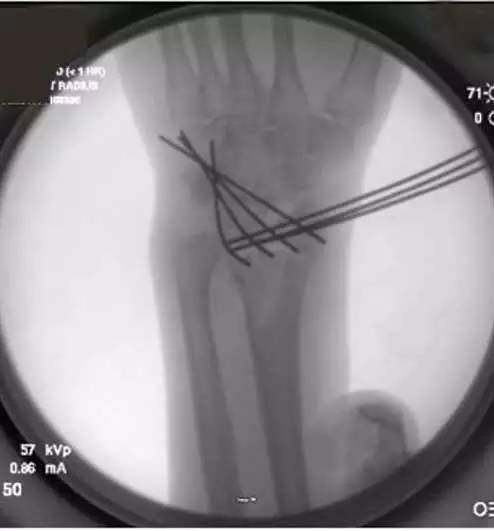

1. 从桡侧向尺侧置入 3 枚平行克氏针,固定桡骨远端的骨折块(图 1)。

2. 在上述克氏针垂直方向(由背侧向掌侧)置入另一组克氏针,并尽可能靠近第一组克氏针,最远可置入桡骨远端关节面软骨下,为后期放置钢板提供空间。(图 1)

图 1 置入克氏针